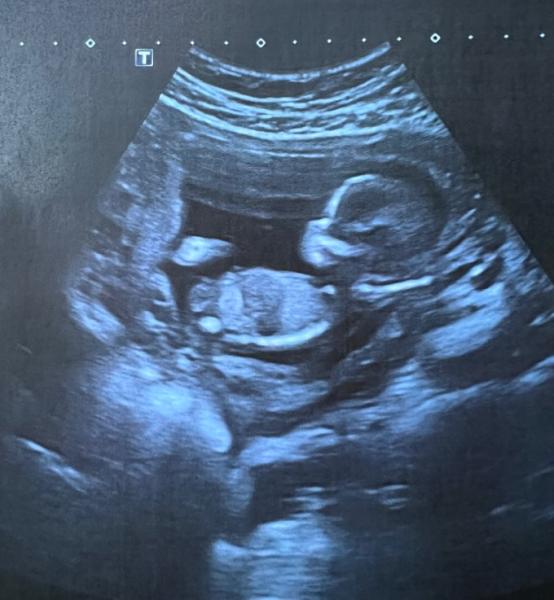

Hey, ich bin so neugierig und wollte euch Mal fragen, ob ihr was erkennen könnt? Das bild ist von der 15. ssw Danke im voraus

Bild zu Geschlecht erkennen - Forum für Juni - Mamis

Ich bin natürlich kein Experte aber ich würd Mädchen tippen

Ja aber ich sehe da keinen Nub. aber ich kenn mich da auch nicht so gut aus

Ich tippe auch auf Mädchen aber bin natürlich auch kein Profi